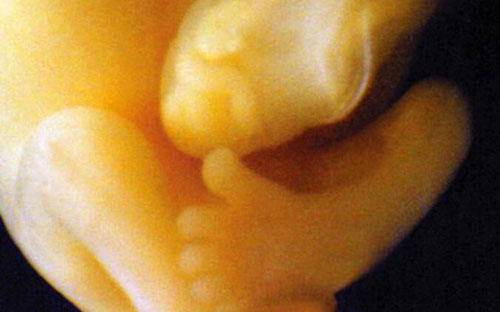

Hình chụp toàn thân một thai nhi chưa phát triển đầy đủ nhưng các bộ phận hình thù cơ bản đã khá rõ.